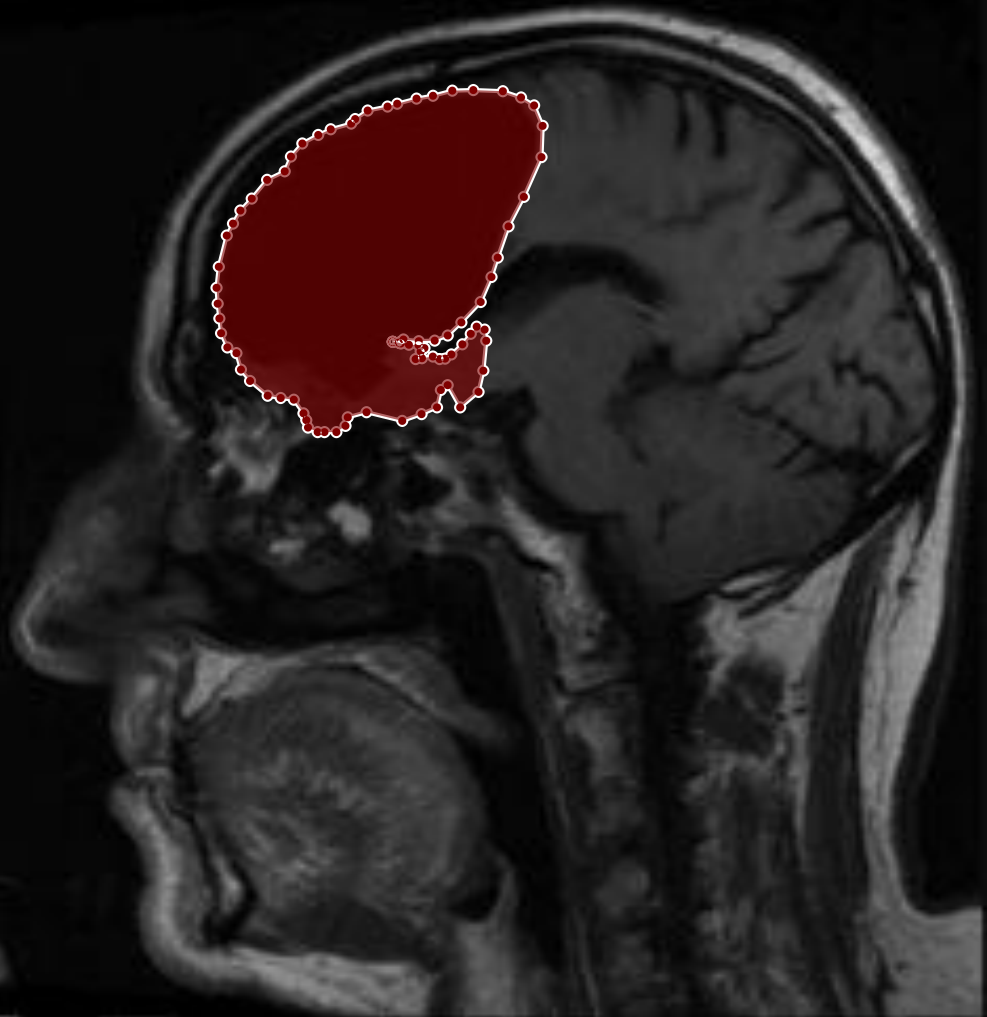

Figure 2: Samples of Meningioma segmentation across different imaging planes

Meningioma: Meningiomas arise from the meninges and are generally well‑circumscribed and homogeneous, making them easier to segment. However, their location adjacent to critical structures such as dural sinuses and cranial nerves can complicate diagnostic tasks. An example of a meningioma and its segmentation mask is presented in Figure 2, illustrating the clarity of its boundaries.